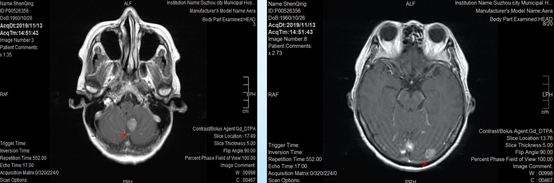

PET-CT示右下肺近肺门占位、两侧胸膜多处转移、肝脏低密度灶,左肾上腺、全身多发淋巴结、全身骨多处均葡萄糖代谢增高,考虑右肺癌伴全身多发转移,右下肺压缩,两侧胸腔积液。头颅增强MRI提示小脑转移灶。

基因检测提示EGFR 19外显子突变,伴随TP53突变。

最终诊断:肺腺癌T3N3M1,IV期,EGFR 19阳性。

由于患者合并TP53突变以及脑转移,因此选择一线奥希替尼80mg qd进行治疗。

由于增强头颅MRI等待时间较长,患者选择头颅CT复查,没有发现转移灶。

头颅增强MRI没有发现头部转移灶,疗效评价疾病稳定(SD)。